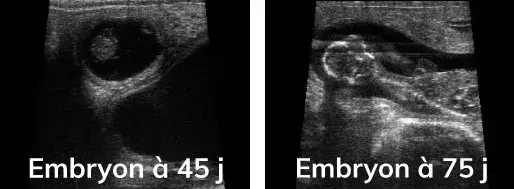

Que la repro se fasse par insémination ou en monte naturelle, les échographies de gestation se font à partir de 35 jours après la fécondation. Les échographies sont suffisamment précises pour assurer des résultats fiables

De déterminer les stades de gestation des femelles pleines (1er tiers, milieu, dernier tiers), grâce à l’aspect et à la taille que présentent les embryons. De cette façon on peut prévoir les futures périodes de vêlage avec une bonne précision. C’est une précieuse information pour mettre en lot les femelles et avoir une gestion optimale de leur conduite : rationnement, surveillance des vêlages, etc...